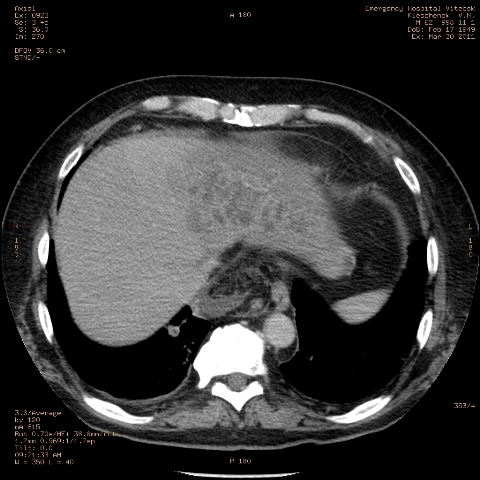

при исследовании органов брюшной полости по поводу абсцесса печени, в нижнем этаже средостения выявлено образование неоднородной плотности (-5-+25), при в/в контрастировании - не контрастируется, при per os - затёков из пищевода нет, неправильно овальной формы. предположительно киста перикарда? спасибо за помощь!

Может быть enteric duplication cyst. Как бы есть грыжа жира hiatal. И что с печенью? Мало срезов.